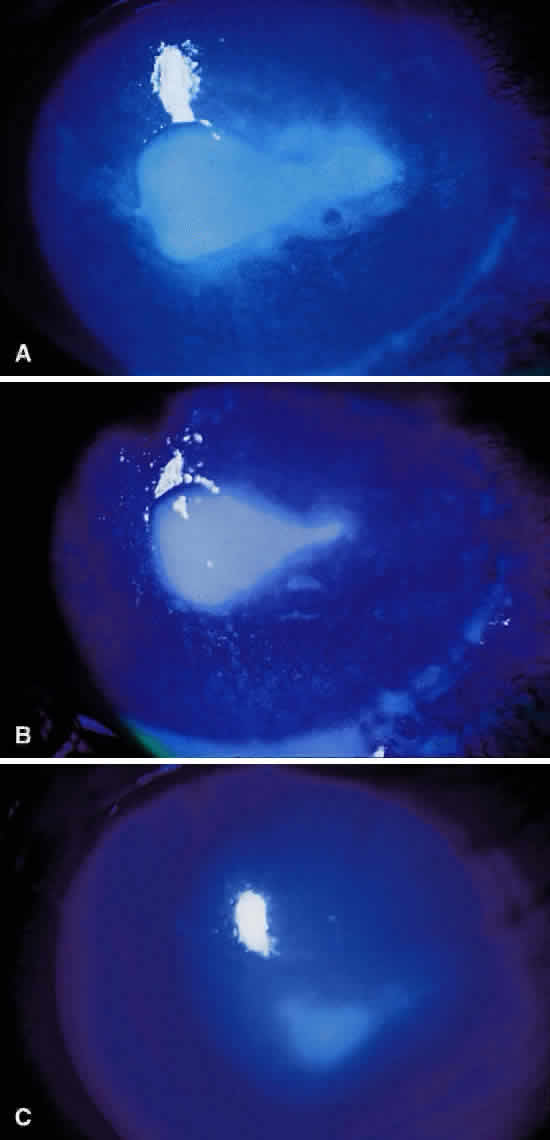

The corneal ulcer at 18 to 24 hours may begin to show subtle signs of improvement if appropriate antibiotic therapy has been instituted. Specifically, evidence of a decreasing epithelial defect (Fig. 19); reduction in the size, density, and edges of the stromal infiltrate (Fig. 20); and a decrease in the surrounding white blood cell reaction (Fig. 21), as well as the anterior chamber reaction, indicate clinical improvement of the corneal infection (Table 6). Recognition of these clinical signs is crucial when beginning the modification of therapy and should be used to reach a therapeutic decision in combination with the preliminary culture results. The clinician should check with the laboratory within 18 hours of obtaining the cultures because tentative bacterial identification is often possible at that time. It is important to note, however, that the initial antibiotics employed should be continued for at least 36 to 48 hours if clinical improvement is observed, despite preliminary results from the laboratory. If, on the other hand, there has been deterioration despite 24 to 48 hours of antibiotic therapy, therapeutic changes should be made based on culture results. In some cases the stromal infiltrate may improve but the epithelium and conjunctiva worsen because of the toxicity of the fortified topical antibiotics. Thus, a patient may have an improved stromal infiltrate in the setting of an enlarged epithelial defect and increased conjunctival chemosis after 24 hours of fortified topical antibiotics.98 This problem may be remedied by reducing the frequency and concentration of the applied antibiotics. The clinician should be aware that many of the concentrated topical antibiotics are potentially toxic to the ocular surface, and a worsening of this aspect of the clinical picture may not reflect a true progression of the microbial keratitis.

Fig. 19. Clinical signs of improvement in the healing of a corneal ulcer: decrease in corneal epithelial defect during treatment of a Serratia marcescens corneal ulcer. A. Initial defect. B. Three days of therapy. C. Ten days of therapy.

Fig. 20. Clinical signs of improvement in the healing of a corneal ulcer: reduction in size and density of the stromal infiltrate and “blunting” of the infiltrate edges with treatment of a Pseudomonas aeruginosa corneal ulcer. A. Initial appearance. B. Two days of therapy. C. Seven days of therapy.

Fig. 21. Clinical signs of improvement in the healing of a corneal ulcer: decrease in surrounding stromal white blood cell reaction during treatment of a Serratia marcescens corneal ulcer. Note also the decreasing epithelial defect. A. Initial appearance. B. Three days of therapy. C. Fourteen days of therapy.